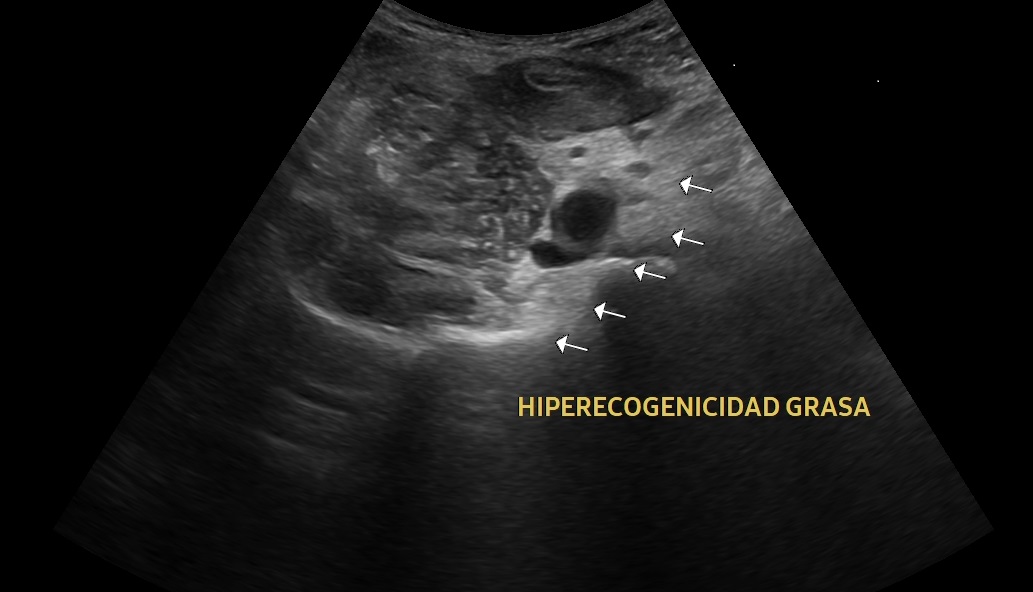

Se realiza una exploración abdominal ecográfica donde se observa hígado de ecogenicidad normal sin lesiones ocupantes de espacio. Vesícula biliar normal, vía biliar no dilatada. Ambos riñones de tamaño y aspecto normales. Páncreas, bazo y aorta normales. En fosa ilíaca derecha se observa apéndice cecal engrosado (imagen 1) con llamativa hiperecogenicidad de la grasa abdominal en relación con cambios inflamatorios (imagen 2). Colección abdominal en relación con cambios inflamatorios 3 x 3 x 5,3 cm (imagen 3).

La ecografía clínica se ha convertido en una herramienta útil para el diagnóstico temprano de apendicitis aguda. Gracias a su accesibilidad, permite realizar una evaluación rápida, ayudando a identificar signos como el engrosamiento del apéndice o la acumulación de líquido periapendicular.